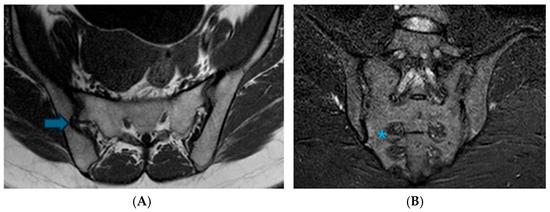

Assessment of Anatomical Variations in the Sacroiliac Joint Using Magnetic Resonance Imaging: A Retrospective Study of 840 Patients

Background/Objectives: This study aimed to examine the prevalence of anatomical variations in the sacroiliac joints (SIJs) as observed through Magnetic Resonance Imaging (MRI), to characterize their manifestations, and to identify MRI features that may resemble inflammatory alterations. Methods: A retrospective review was conducted on consecutive MRI scans of the SIJ performed from January 2009 to January 2022. Eight anatomical variations, along with associated edematous and structural changes, were assessed. Results: The study encompassed 840 patients, with anatomical variations identified in 39.7% of the cohort, occurring more frequently among female participants. The most prevalent variations were accessory SIJ (36.2%) and the iliosacral complex (32.2%). Notably, isolated synostosis and persistent ossification center variations were absent. The increased frequency of variations in women, as well as their correlation with advancing age, was statistically significant (p = 0.034). Accessory SIJ and dysmorphic alterations were linked to bone marrow edema and structural modifications. In the iliosacral complex and semicircular defect variations, prominent vascular structures were observed extending along the bone surfaces. The number and depth of edema slices in sacroiliitis exceeded those observed in the variation (p < 0.001). Conclusions: Anatomical variations of the SIJ are prevalent among women and tend to increase with advancing age. Given that these variations, particularly accessory SIJ and dysmorphic alterations, may present with edematous and structural signal intensity changes that resemble sacroiliitis, it is crucial to recognize these variations. It is recommended to assess axial and coronal images concurrently and to exercise caution in the interpretation of SIJ MR images. Full article

Show Figures

Figure 1